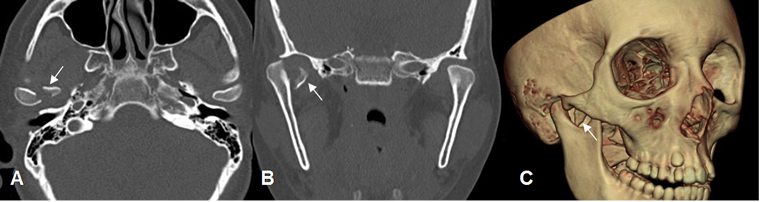

Fig 19. Trauma.

A: TAC axial y B: TAC reconstrucción coronal. Subluxación del cóndilo mandibular derecho. Adicionalmente hay fractura, con desplazamiento medial del fragmento.

C: TAC reconstrucción 3D. Fragmento óseo suelto.